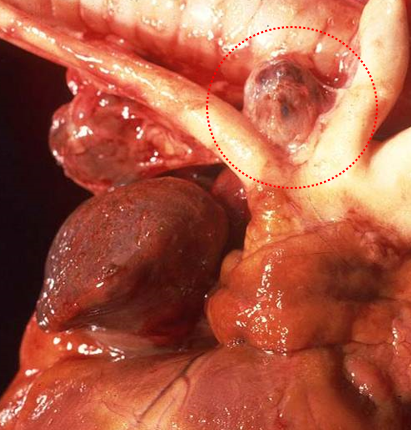

Where will you often find a haemangiosarcoma?

Right atrium in dogs, spleen in dogs

How does a haemangiosarcoma present grossly and histologically?

Gross – similar to haemangioma

Histologically - scattered, elongated plump neoplastic endothelial cells